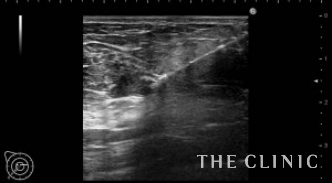

No.31でご紹介した方のオイルシストです。

右に13個・左に8個あり、それぞれ3㎜~15㎜の大きさです。

エコー下にて、穿刺吸引を行います。

全てのしこりを除去できました。